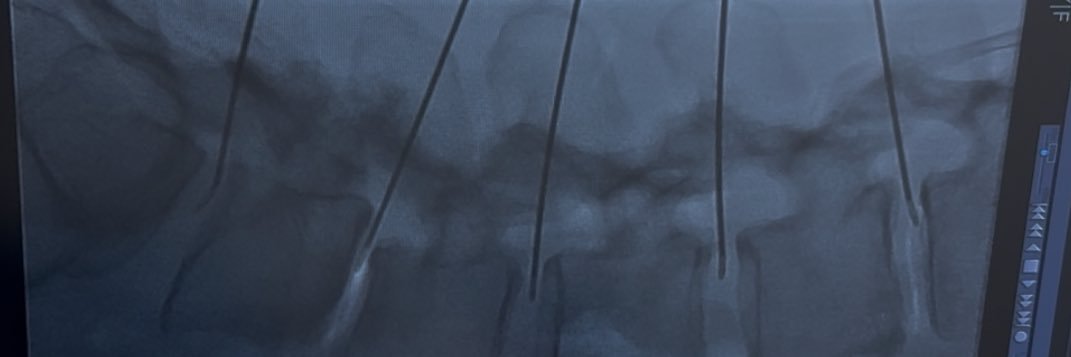

長年の座骨神経痛は、椎間板ヘルニアと狭窄症とすべり症になっていた。投薬治療なしで保存療法を選び、1ヶ月後にアメリカ生まれの椎間板治療をやり、今後どうなるかの記録です。 で、腰が良くなってきたら仙腸関節かと思いきや、梨状筋症候群のような症状でてきて座れない